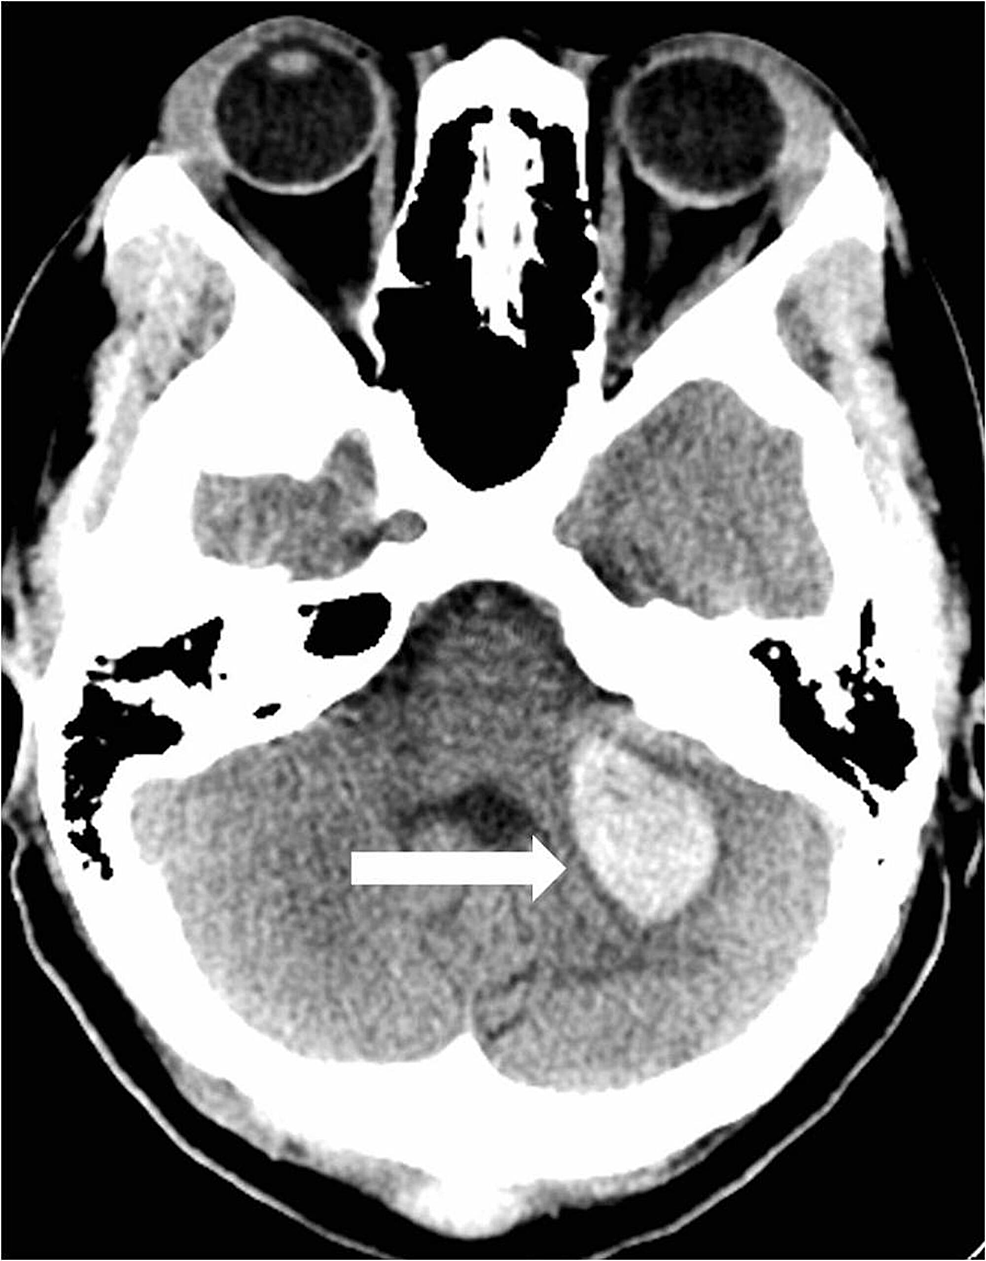

A 39-year-old female with a history of posterior fossa AVM, AIDS, and hypertension presented with headaches, dizziness, blurry vision, and left-sided facial numbness. She had a previous history of hemorrhage from an AVM in the posterior fossa which was treated with a partial embolization two years prior. She was scheduled for a resection of the AVM at that time but was lost to follow up. Physical exam showed no abnormalities on admission. CT scan of the head showed an acute parenchymal hemorrhage in the inferior left cerebellum (Figure 6).